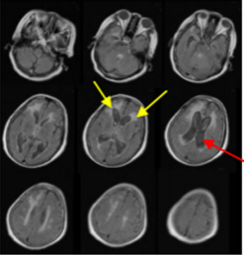

颅脑MRI:脑室扩大(红色箭头),脑积水形成,脑室周围渗出明显(黄色箭头)

然而在开颅手术治疗后4月,能独立行走,生活自理的她,突然变得需要在家人搀扶下,才能勉强下地行走,反应变得稍微迟钝,对近期事情记忆困难,无法做简单的计算题,甚至出现了大小便失禁。家人将其再次送诊我院,先后行颅脑CT及MRI,提示“脑室较前明显扩大,脑室周围渗出明显”,证实了“颅内出血后脑积水”形成,并明确其正在缓慢进展中,完善“腰穿脑脊液释放试验”后,又能下地行走,提示了“脑脊液引流治疗,对患者治疗有效”,